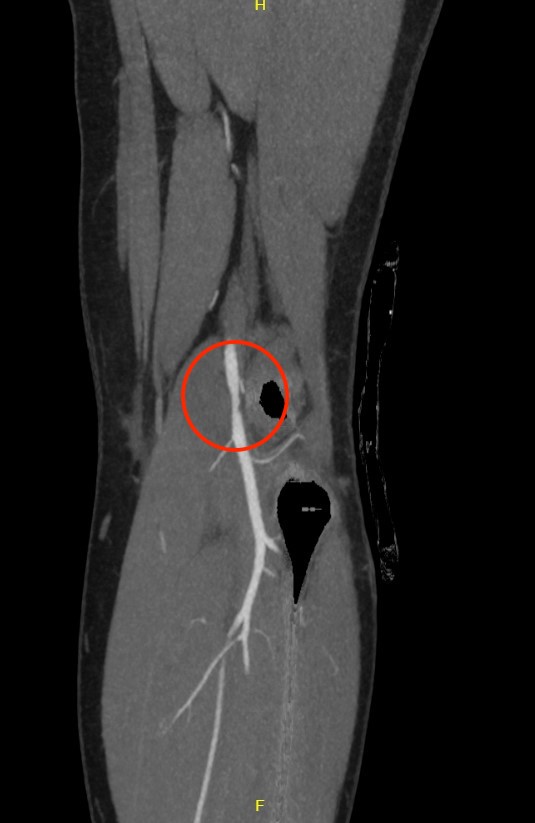

Normal CT angiogram Popliteal artery stenosis following knee dislocation

Popliteal artery transection following left knee dislocation

Advantages

- readily available, non invasive

- extremely accurate

- also used confirm the site and mechanism of injury

- multi-detector CT

- 100% sensitive and specific in detecting clinically significant arterial injury

Gakhal et al. Vascular and Interventional Radiology 2009

- CTA signs of lower extremity vascular trauma